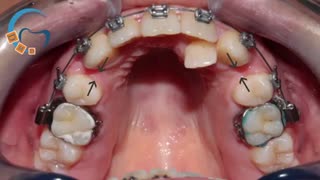

ارتودنسی ثابت و متحرک نامرتبی دندانی و دیپ بایت شدید بدون کشیدن دندان